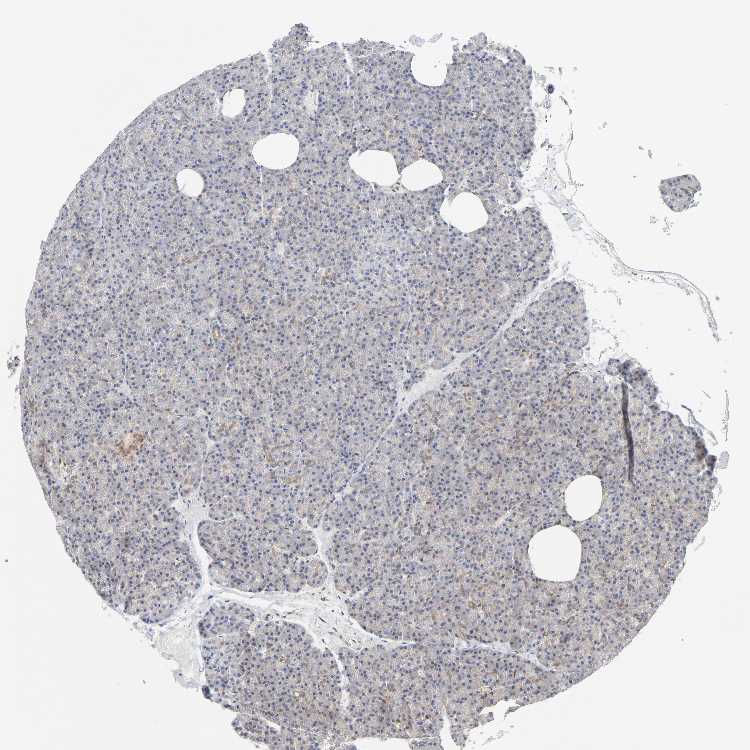

PANCREAS - Antibody stainingi

Antibody staining in the annotated cell types in the current human tissue is reported as not detected, low, medium, or high, based on conventional immunohistochemistry profiling in selected tissues. This score is based on the combination of the staining intensity and fraction of stained cells.

Each image is clickable and will lead to virtual microscopy that enables deeper exploration of all samples and also displays staining intensity scores, fraction scores and subcellular localization as well as patient and tissue information for each sample.

Antibody HPA031335Antibody CAB004076Antibody CAB080153Antibody CAB080157

Exocrine glandular cells MediumNot detectedMediumMedium

Pancreatic endocrine cells MediumLowHighLow